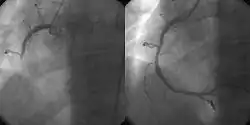

Podczas PCI po nakłuciu tętnicy udowej, promieniowej lub ramiennej wprowadza się cewnik zakończony balonem do ujścia odpowiedniej tętnicy wieńcowej i umieszcza pod kontrolą rentgenowskiego toru wizyjnego w obrębie zwężenia. Balon wypełniany jest pod ciśnieniem rozcieńczonym środkiem kontrastującym w celu poszerzenia zwężonego odcinka, po którym wykonuje się ponownie angiografię w celu udokumentowania efektu poszerzenia. PCI często wykonywane jest w zależności od potrzeb w 2 lub 3 naczyniach. W ostrym zawale mięśnia sercowego PCI wykonuje się tylko w naczyniu zawałowym pozostawiając ewentualne inne zmiany do usunięcia w późniejszym terminie[1].